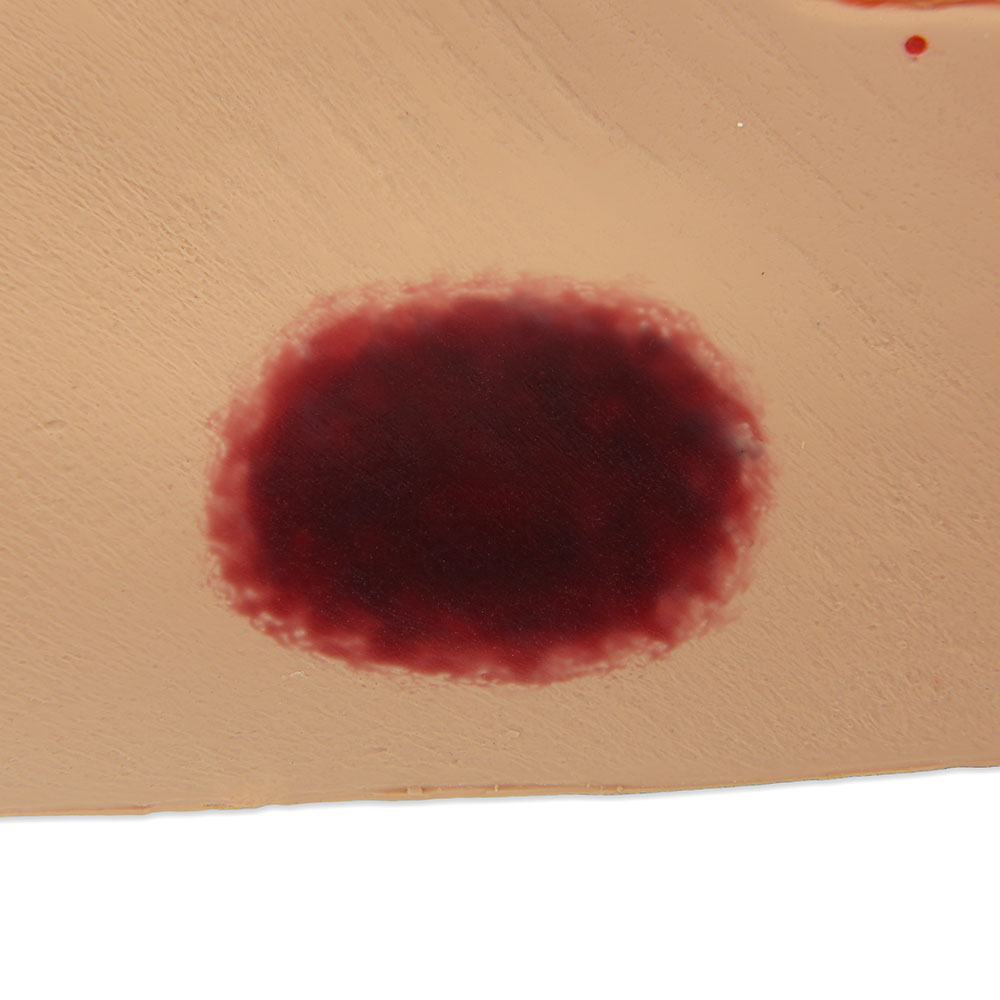

- Wound care simulation model displays the following pressure injuries:

- Stage 1

- DTPI (Deep Tissue Pressure Injury)

- Great care has been taken to hand paint each wound just as you would see it on a patient for the most life-like patient training scenario